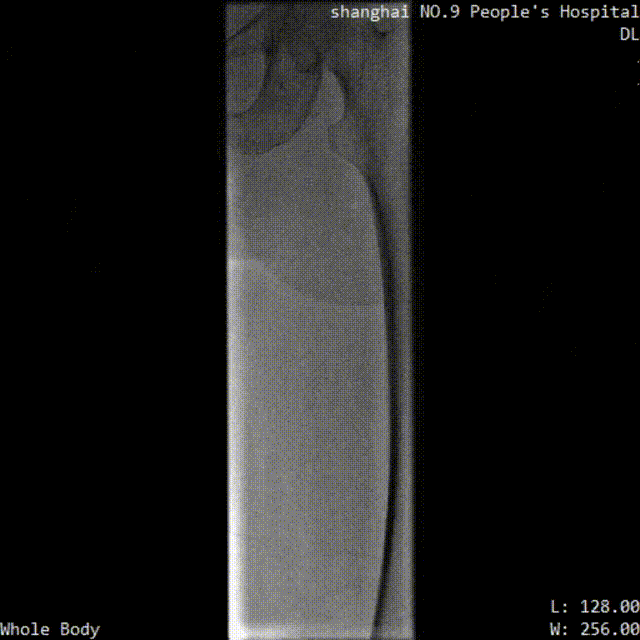

■ LuVoCaptor取栓前后管腔造影對照:

取栓術前管腔造影

取栓術后管腔造影